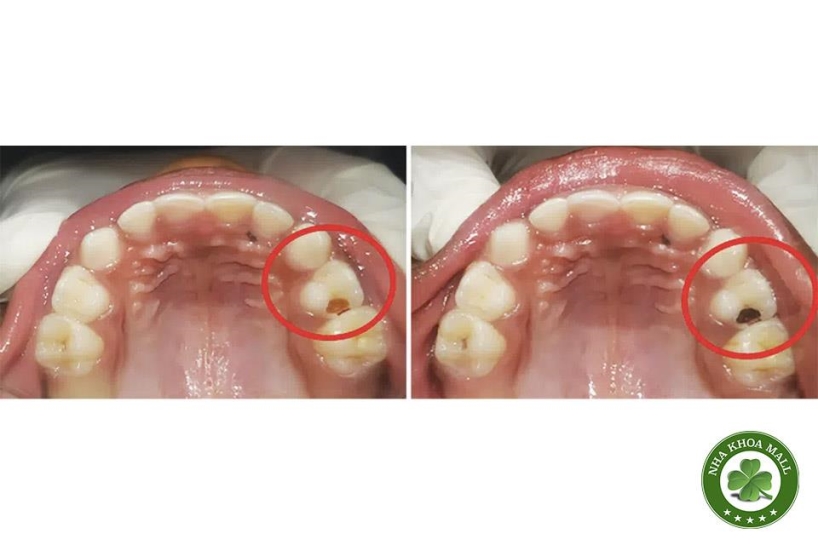

SDF có thể gây nhuộm đen mô sâu răng – tuy nhiên, ở vùng kẽ, điều này không ảnh hưởng đến thẩm mỹ.

Có thể bôi GIC tạm hoặc nhựa phủ mỏng (resin coat) sau SDF nếu cần thẩm mỹ cao (Kumar J et al., Int J Paediatr Dent 2019).